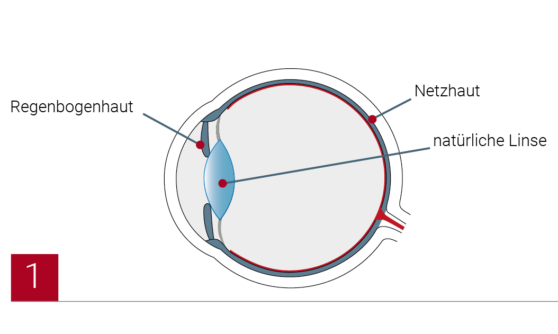

Die Operation wird ambulant vorgenommen und dauert in der Regel 15 Minuten pro Auge. Vor dem Eingriff wird das Auge mit Tropfen betäubt, sodass der Patient beim Linsenaustausch keine Schmerzen spürt. Das Auge wird mit einem winzigen Hornhautschnitt geöffnet, der nahtlos verheilt.

Die vordere Linsenhülle wird kreisrund geöffnet. Dann wird der Linsenkern entfernt. Der Rest der Linsenhülle bleibt erhalten und dient als ‘Halteapparat’ für die neue Linse.

Die Operation wird ambulant vorgenommen und dauert in der Regel 15 Minuten pro Auge. Vor dem Eingriff wird das Auge mit Tropfen betäubt, sodass der Patient beim Linsenaustausch keine Schmerzen spürt. Das Auge wird mit einem winzigen Hornhautschnitt geöffnet, der nahtlos verheilt.

Die vordere Linsenhülle wird kreisrund geöffnet. Dann wird der Linsenkern entfernt. Der Rest der Linsenhülle bleibt erhalten und dient als ‘Halteapparat’ für die neue Linse.